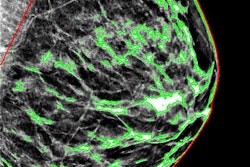

The American College of Radiology (ACR) has released an updated version of its 2016 Digital Mammography Quality Control Manual.

The manual helps users develop and implement quality control (QC) programs for digital mammography equipment, and it outlines the responsibilities of radiologists, radiologic technologists, and medical physicists, according to the college.